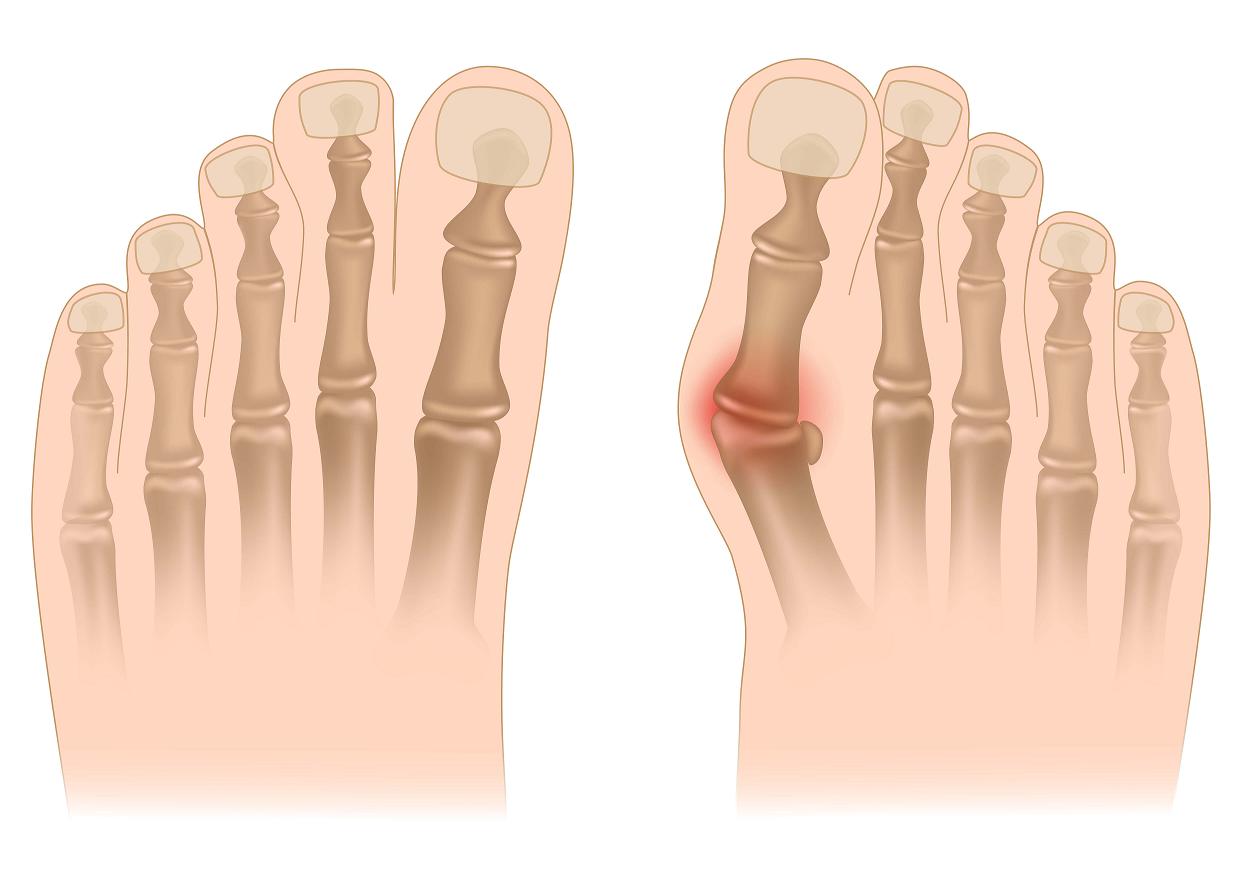

Halluxy, bądź paluchy koślawe, to jedna z bardziej powszechnych dolegliwości ortopedycznych występujących przede wszystkim u kobiet. Po 50. roku życia haluksy występują średnio u 1 na 40 kobiet.

W zaawansowanym procesie deformacji stóp- paluchach koślawych (Halluxach) leczenie operacyjne polega na : ścięciu wyrośli kostnych na głowie I kości śródstopia, usunięcia zmienionej zapalnie kaletki powstałej z powodu ucisku obuwia na paluch, skorygowaniu koślawego ustawienia palucha i zwężeniu stopy.